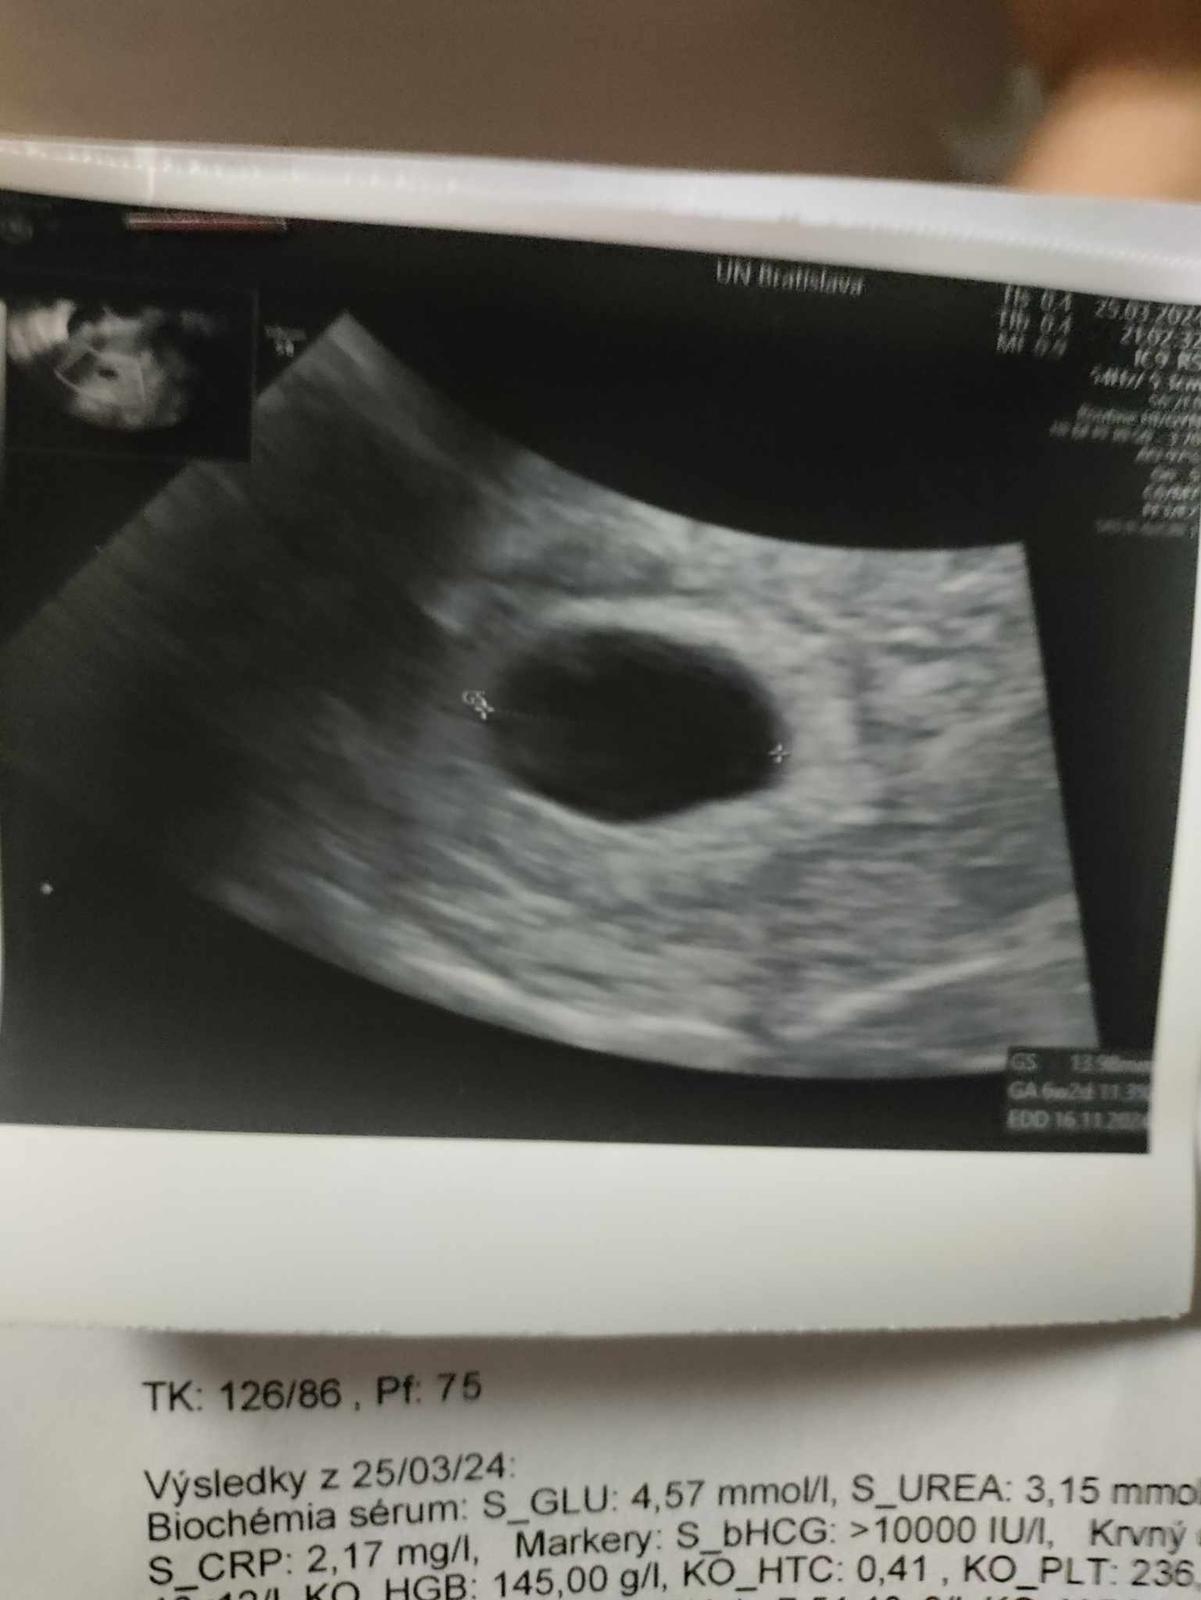

Ahoj baby mali ste niektorá z týmto skúsenosti podľa ms by som mala byť v 7 týždni,podľa ultrazvuku som v 5-6tt včera krv na Pohotovosti brali a hcg je 10000 a na ultrazvuku ešte nič nevideli len gestačný vačok o dva týždne ževraj kontrola u lekára ,ten vačok pred týždňom mal len 8 mm včera už 13,98 mm

Takto mi dal lekár len ultrazvuk prázdny gestačný vačok